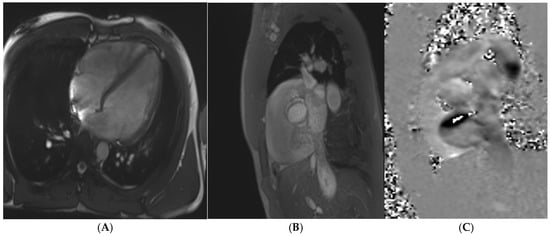

Cardiac MRI plays a key role in the diagnostic evaluation of athletes in the ‘grey-zone’. Cardiac MRI is the gold standard for evaluating chamber dimensions and global and regional systolic function of both ventricles [78]. The degree of ventricular dilatation is also helpful from a diagnostic perspective. A very dilated LV > 60mm in end-diastolic (LVIDd) is only present in 15% of elite athletes [36], dropping to <1% if exceeding 70mm [43]. Cardiac MRI reference ranges specific to athletes, derived from meta-analysis, can contribute to identifying individuals with extreme remodelling patterns [30]. The relationship between the LV and RV can also help discriminate between a physiologically vs. pathologically dilated ventricle (Figure 5). Proportionally dilated ventricles favour athletic remodelling, provided this tallies with the demographic and training profile of the athlete.

Figure 5. A 21 year old Caucasian male found to have lateral T-wave inversion on pre-recruitment ECG to join the military. Echocardiography showed dilated left and right ventricles, a bicuspid aortic valve (AoV), and possibly an atrial septal defect (ASD). Cardiac MRI confirmed the presence of dilated ventricles (A) exceeding reference ranges for male athletes. A bicuspid AoV (Sievers Classification Type 0) was also confirmed (B), without regurgitation. Phase-contrast flow imaging confirmed the presence of an ASD (C). Post-contrast imaging showed no replacement fibrosis.